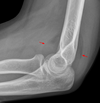

1

Normal XR elbow